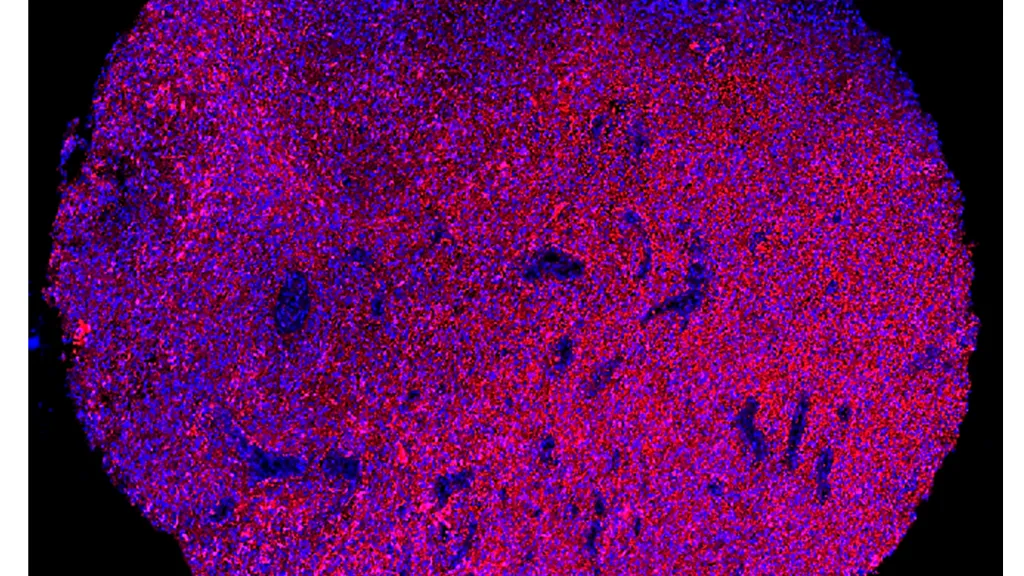

Immunofluorescence staining of a representative human glioblastoma tissue section. In red, the PTPRZ1 markers, and in blue, the cell nuclei. (scale bar: 400 μm) © Denis Migliorini - UNIGE/HUG

Thursday 26 September 2024

Programming cells to target brain tumours